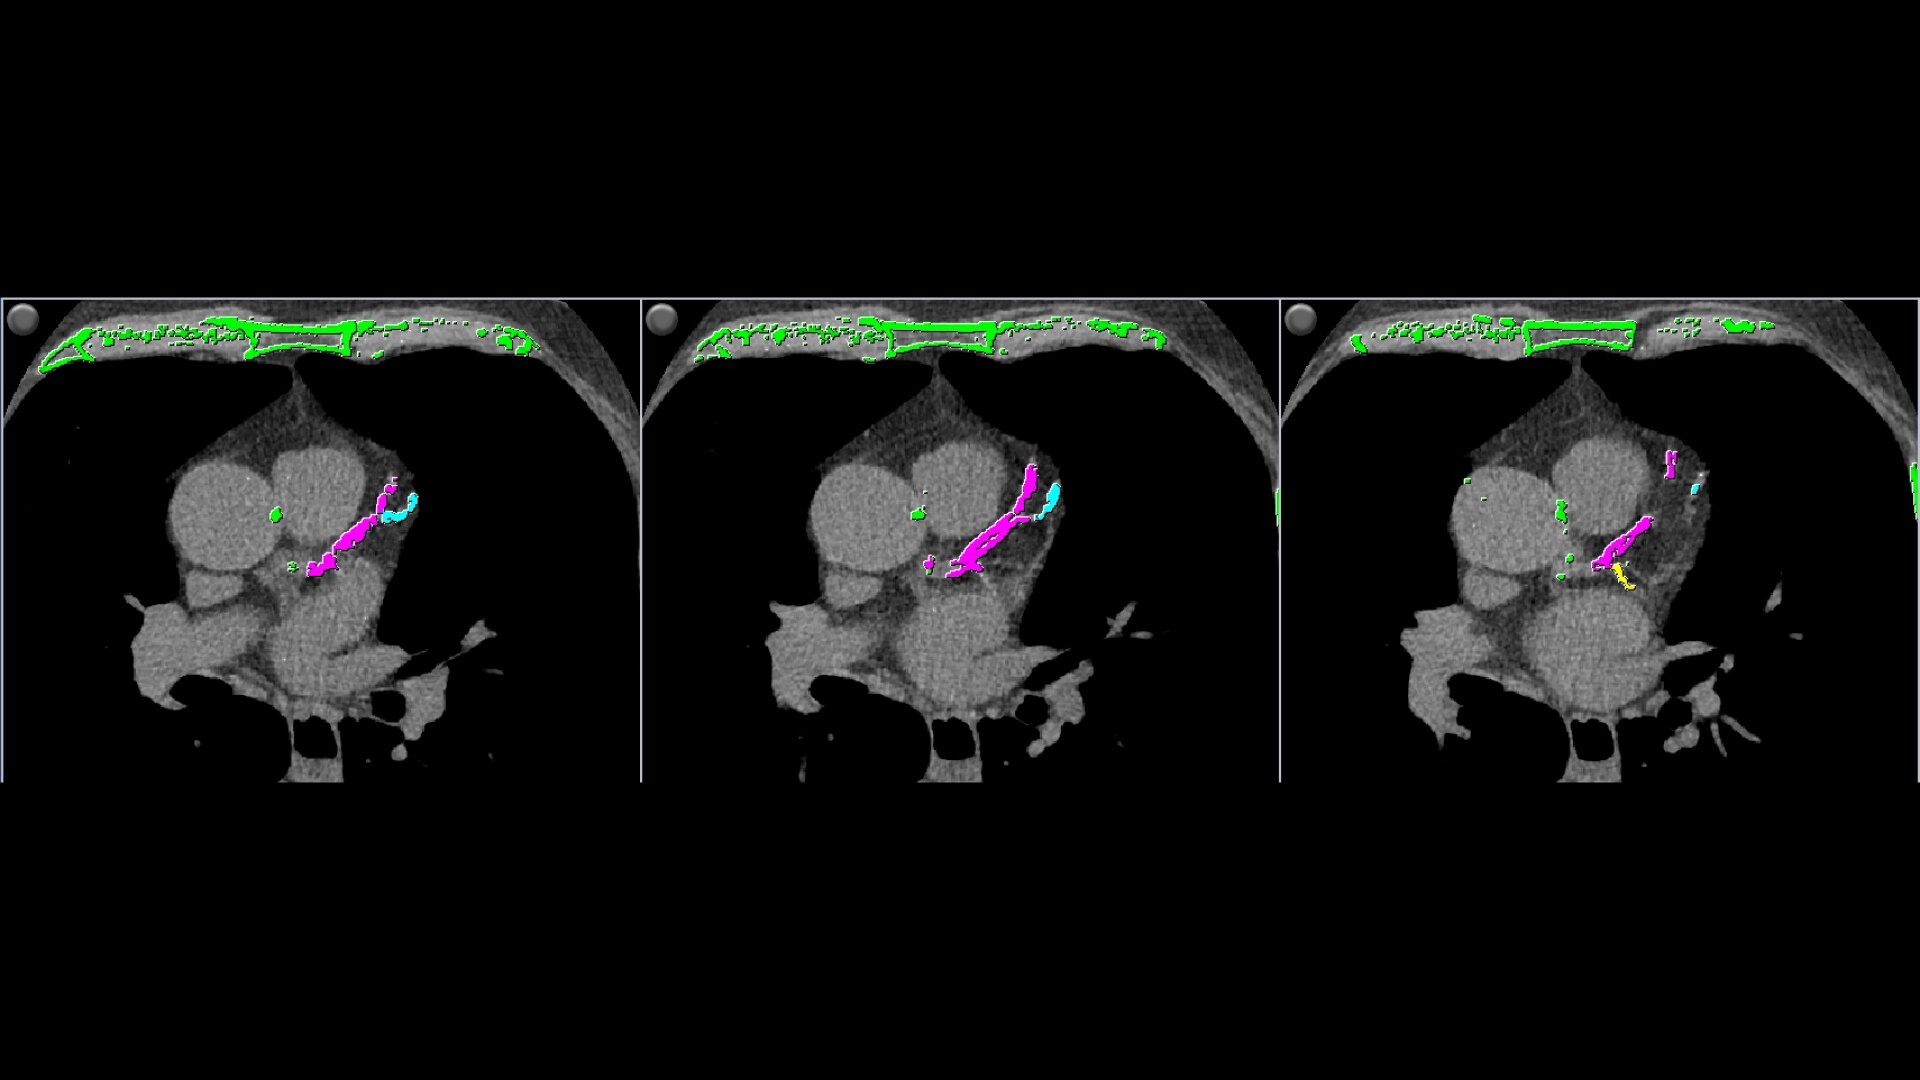

• Automatically detects calcium and highlights it in green

• AJ 130 scoring method uses conventional Agatston/Janowitz technique with a threshold of 130

• HU which is adjusted to the appropriate image slice thickness

• Provides two methods of calcium scoring